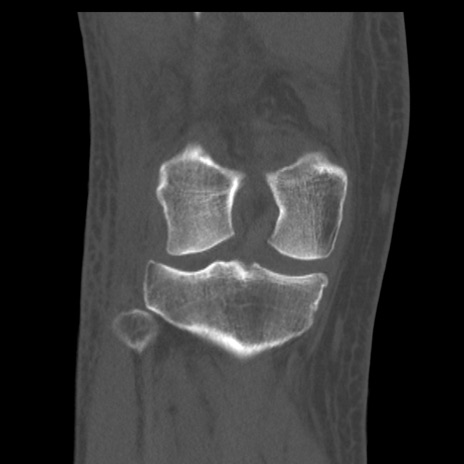

症例28 右膝関節CT(冠状断像)

右膝関節CT

横断像